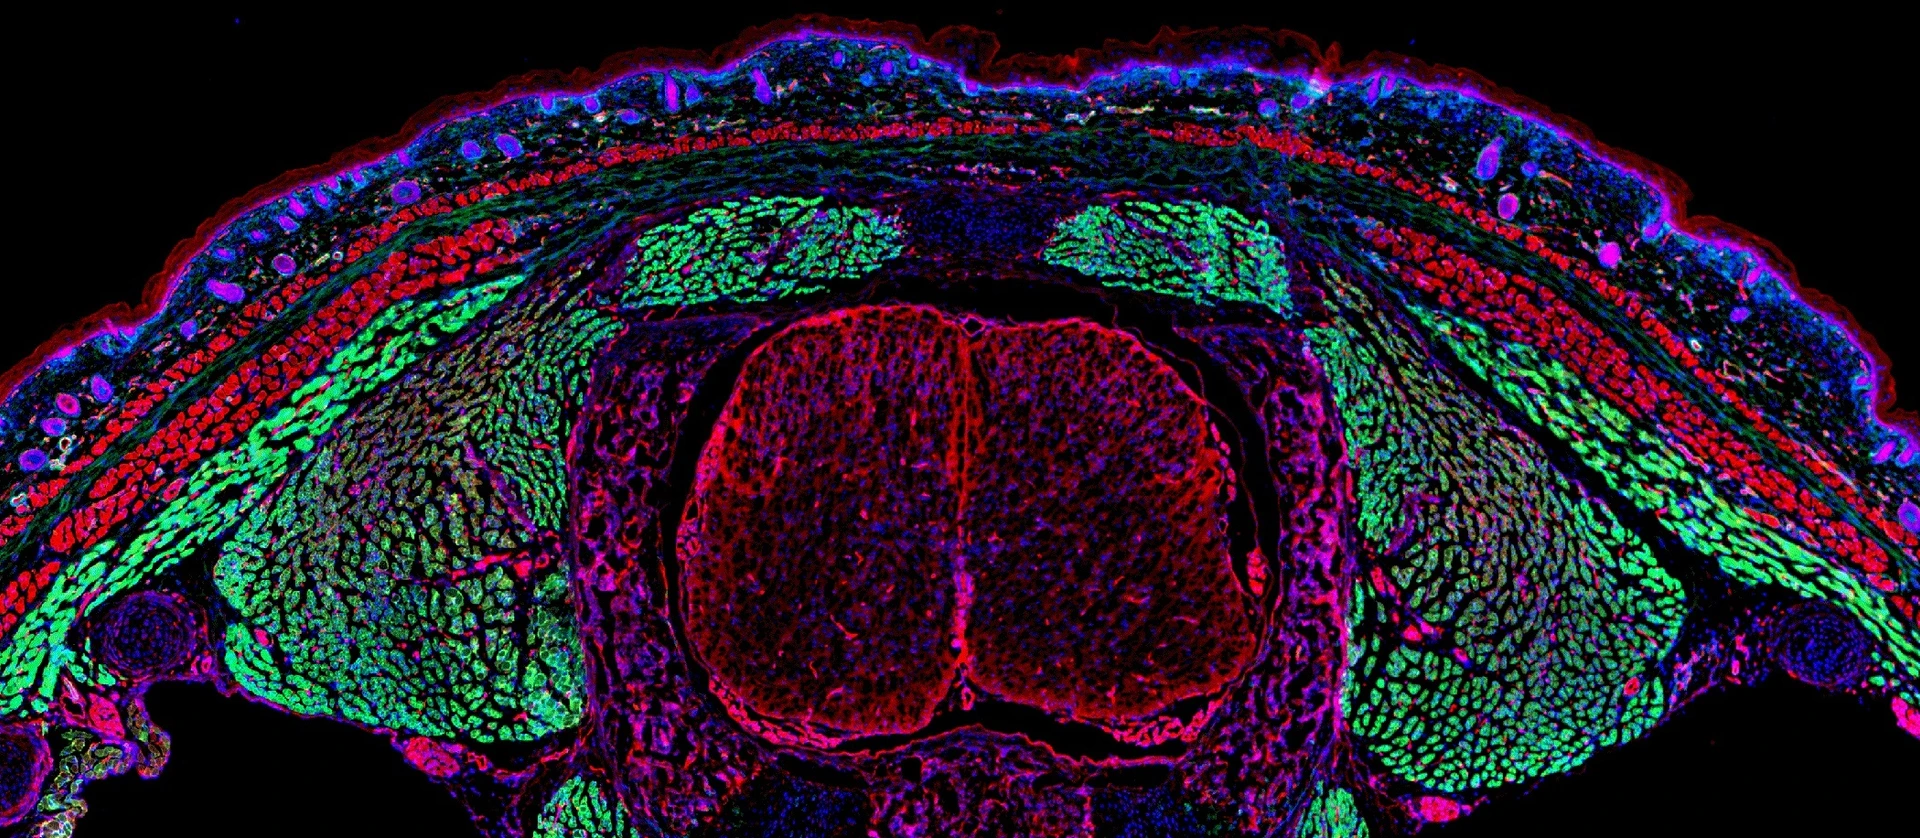

Chimeric grafts to study the contribution of the subcutaneous fascia_red_and skin cells _green_ during the wound healing_scarring process.Nature

Fascia cells (green) rising into dermal open wounds dragging their surrounding matrix (magenta)